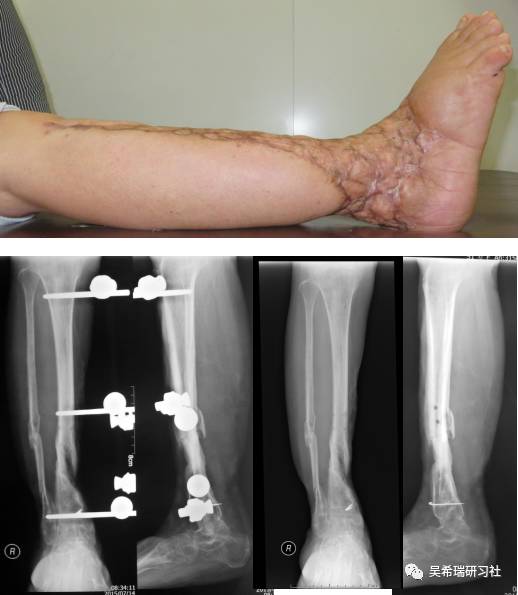

病例7

小腿骨折继发感染骨髓炎反复皮瓣9个月未下地骨质疏松继发肥胖

TIPS:9个月反复皮瓣未下地骨质严重疏松病灶清除后应用表面羟基磷灰石涂层骨圆钉半开放植骨 + 骨搬移骨水泥设计为自行吐出伤口开放换药走路骨质改善、骨愈合治疗足下垂